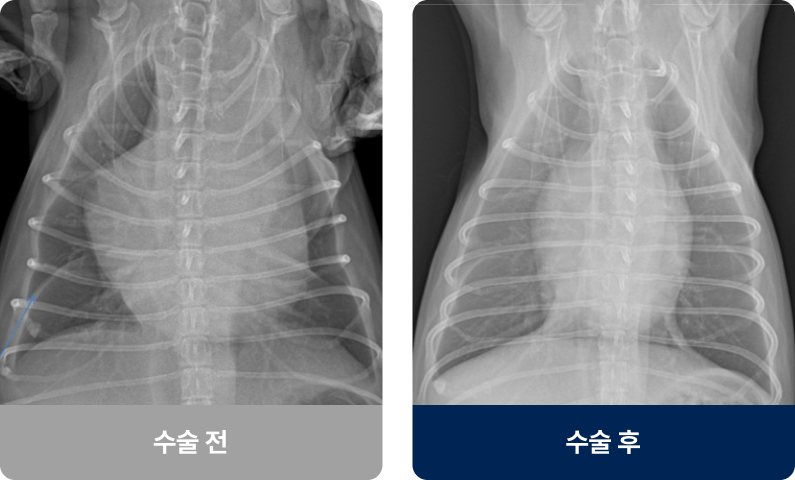

태아 때 심장에서 폐로 가는 ‘동맥관’이 출생 후에도 닫히지 않은 상태로, 이 통로로 혈액이 비정상적으로 흐르며 심장 비대·심부전·폐동맥 고혈압으로 이어질 수 있습니다. 주로 어린 강아지에게 발병률이 높으며, 기침·성장 부진·개구호흡·청색증을 보입니다.